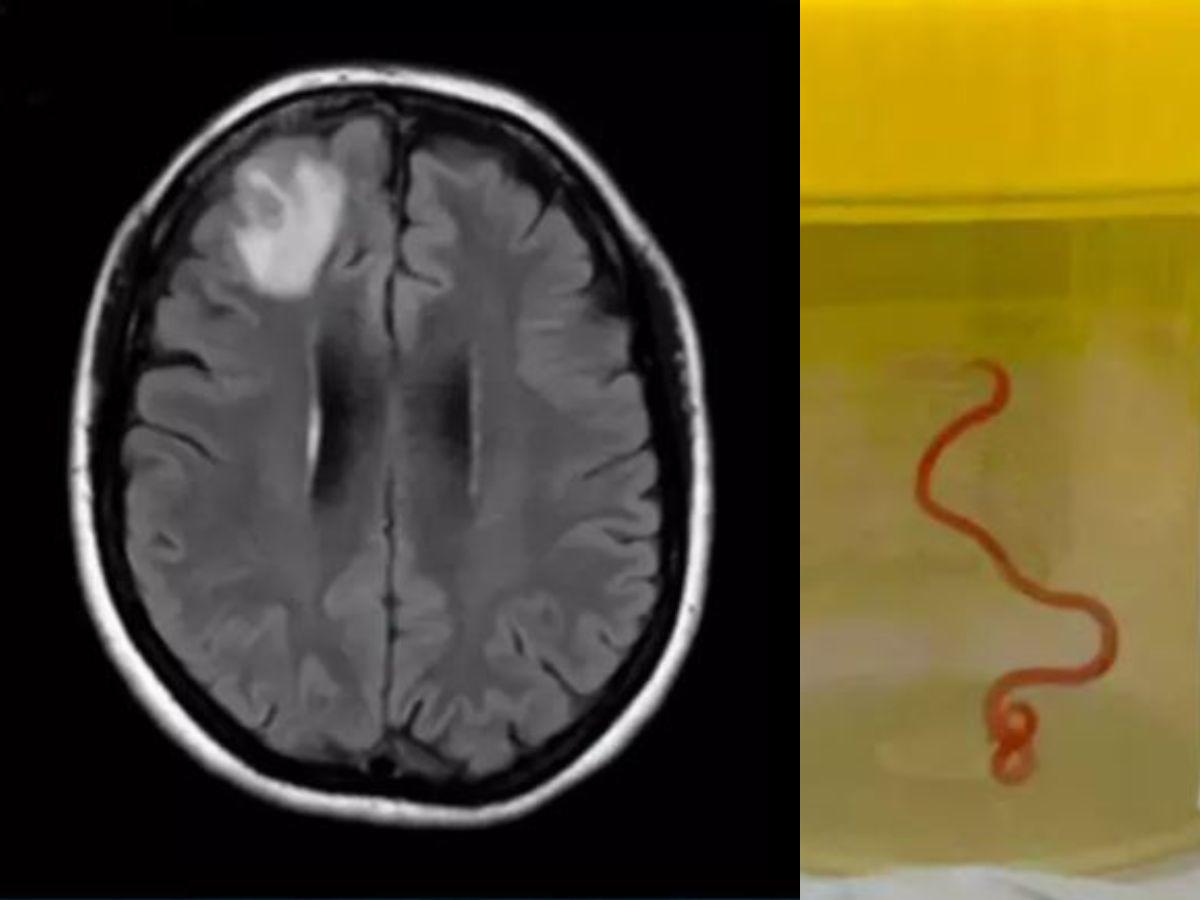

Lo que el doctor encontró dentro de su cerebro era impensable, tanto que ni el propio médico se lo esperaba: un gusano vivo retorciéndose en el cerebro de la mujer y nada menos que 8 centímetros de largo.

La paciente de 64 años sigue bajo supervisión médica recuperándose y su caso está dando la vuelta al mundo por lo insólito, ya que no se conocía nada igual.

Enviaron el gusano a un laboratorio y allí fue donde establecieron que no se trataba de una lombriz intestinal, como creían al principio, sino que era una Ophidascaris robertsi, un parásito que generalmente se encuentra en el esófago y el estómago de las pitones diamantina o ‘pitones de alfombra’.